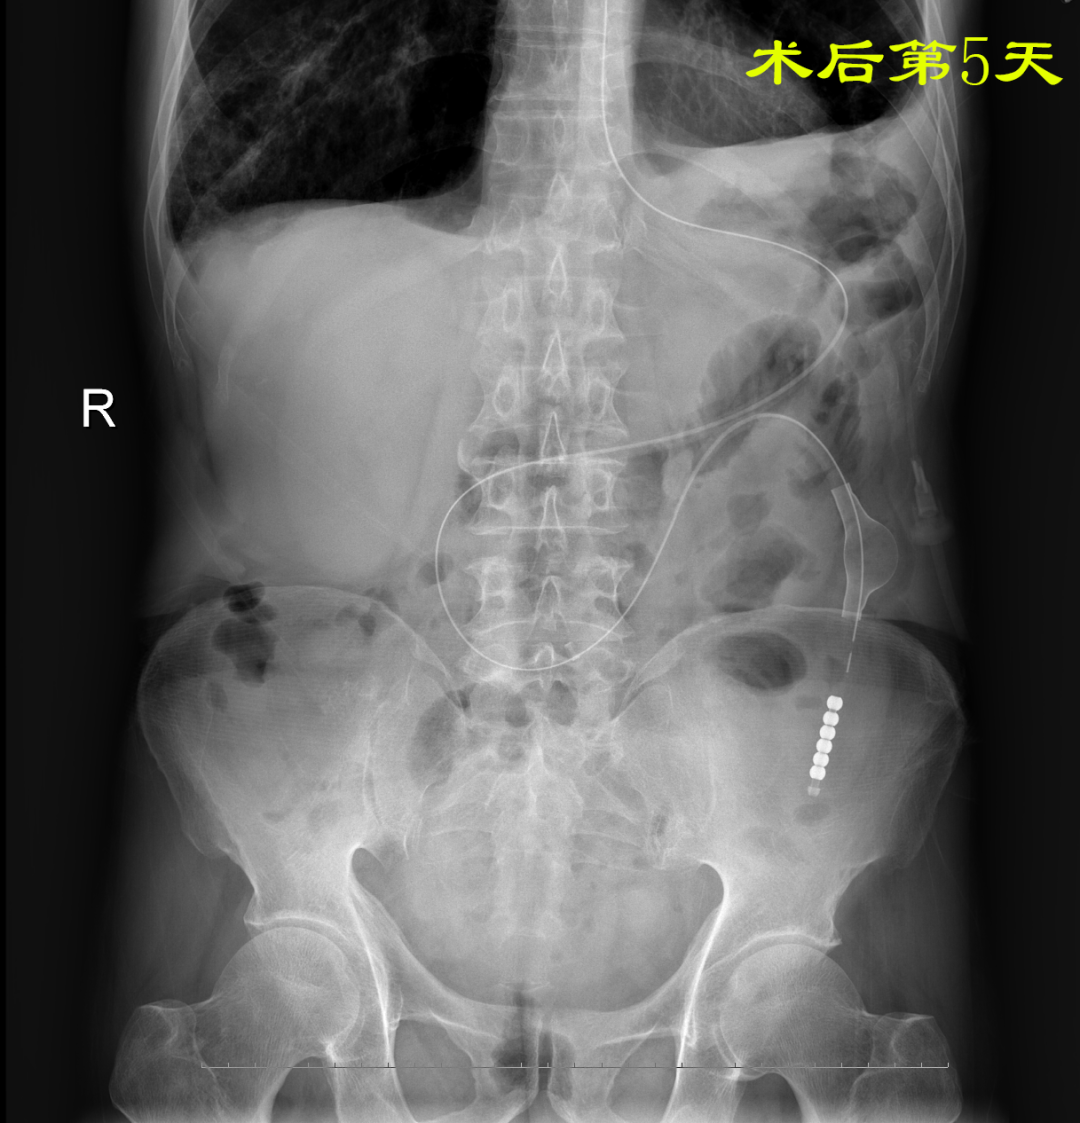

病例:患者男性,74岁,因“腹痛、腹胀伴呕吐、肛门停止排气排便20小时”于2021年7月24日入住我院普外科。患者1月前因回肠穿孔于我院普外科手术治疗,入院后明确诊断为术后粘连性小肠梗阻,经胃管引流等保守治疗无好转。因患者有严重心肺疾患,再次手术风险较大,并且术后再发粘连性肠梗阻的可能性也很大。经过与患者家属沟通后,最后决定采用胃镜引导下置入经鼻插入型肠梗阻导管技术来治疗肠梗阻。由我院消化内科副主任医师杨开余完成操作,耗时大约40分钟,患者术后第5天开始排气排便,腹痛、腹胀症状迅速消失,术后第7天拔除肠梗阻导管,恢复饮食。拔管至今已10天,患者已出院。随访患者无腹痛、腹胀,排便正常。

良好的引流是治疗肠梗阻的基本措施,低位小肠梗阻置入胃管引流常难以奏效,以往大多需要再次手术,而再次手术后粘连的几率高达70%。经鼻插入型肠梗阻导管就是将一根3米多长,内有四个腔道的管道置入十二指肠后,在重力和肠道蠕动的作用下,导管先端部将自动向前运动,直至到达梗阻部位。在导管到达梗阻部位后,可进行双对比造影检查了解狭窄病因,也可以对狭窄处进行扩张,还可以作为支架起到肠排列的治疗效果。肠梗阻导管治疗小肠梗阻属于微创型手术,具有痛苦小、疗效好、费用低、预防再次粘连等优点。